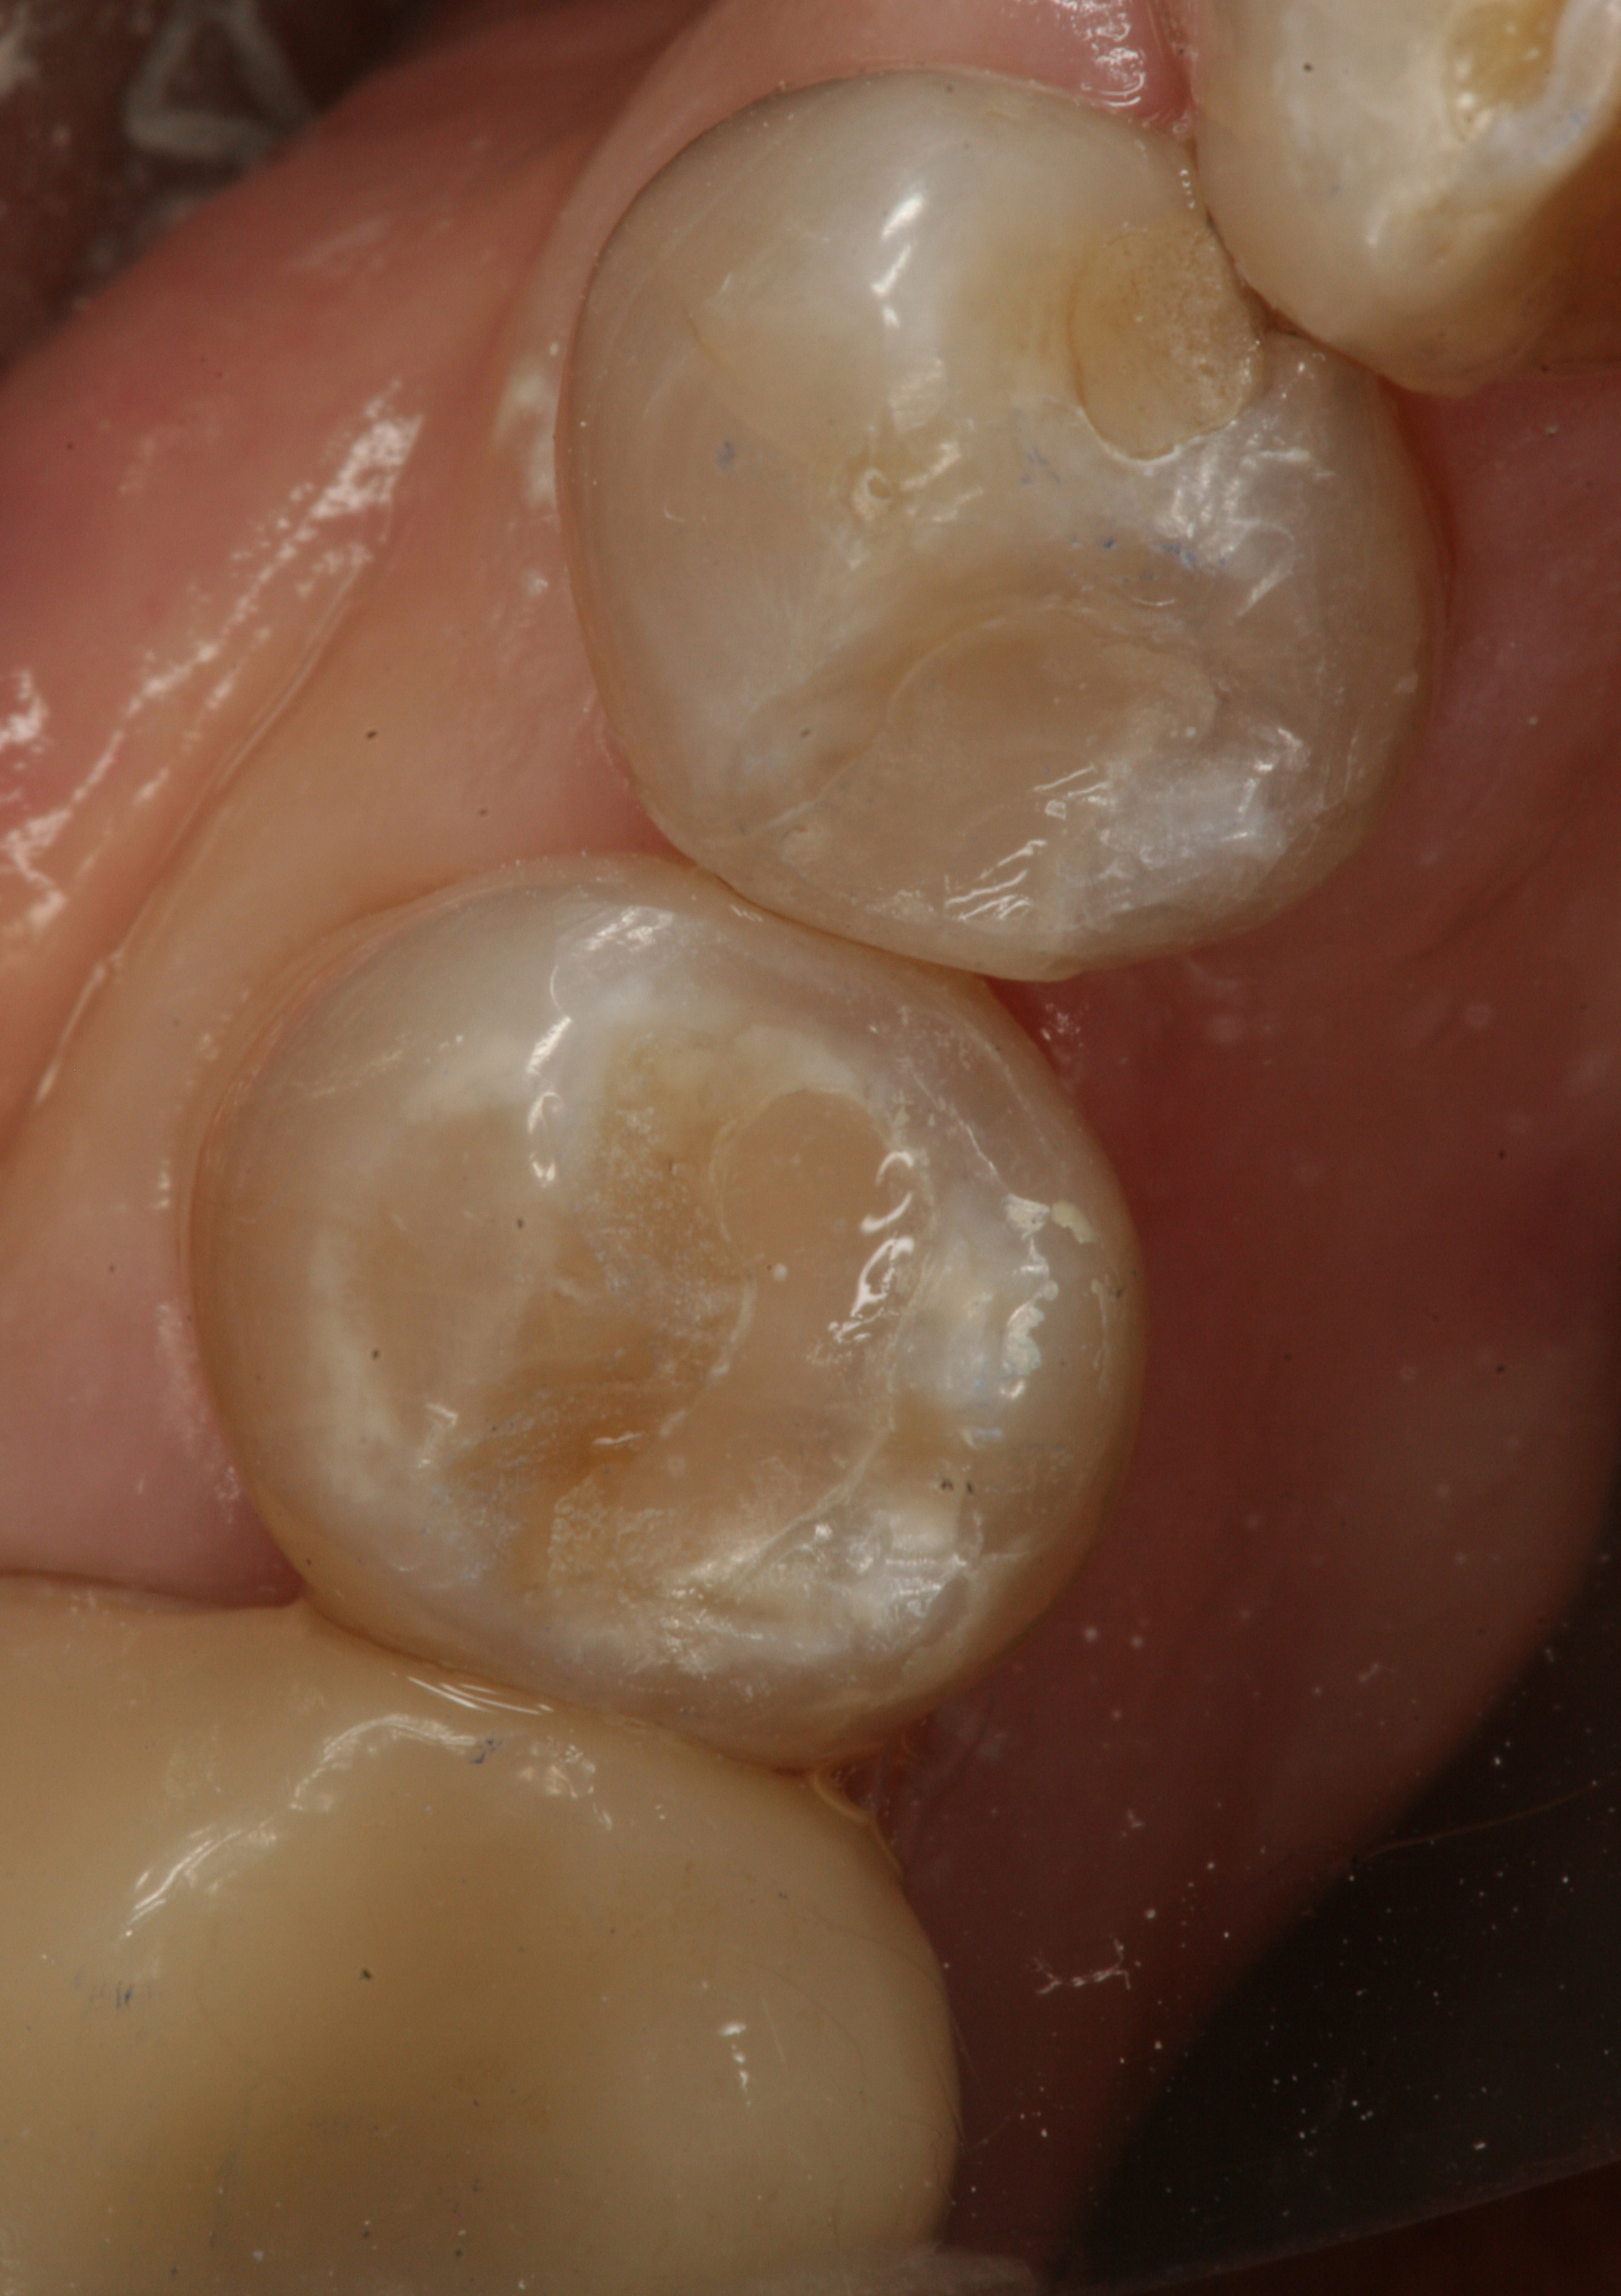

Fig 2. Class I cavity preparation. Note the dark pulpal floor.

Figure 2

Fig 3. Postoperative view after placement of a smart-matching composite without the use of a stainblocker.

Figure 3